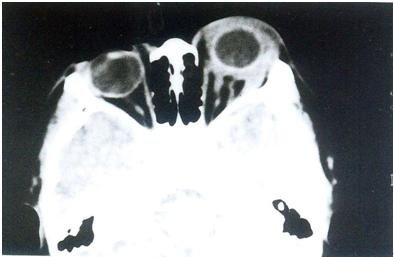

特发性眼眶炎性假瘤CT(巩膜周围炎)

特发性眼眶炎性假瘤CT(巩膜周围炎):左眼眶内病变沿巩膜增生,巩膜增厚